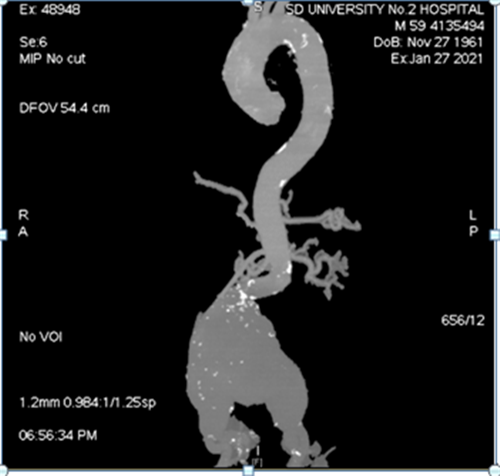

双侧股动脉中低分叉,双侧髂总动脉-胸主动脉动脉见大量钙化团块,部分

mip图像,清晰显示腹主动脉壁多发钙化.